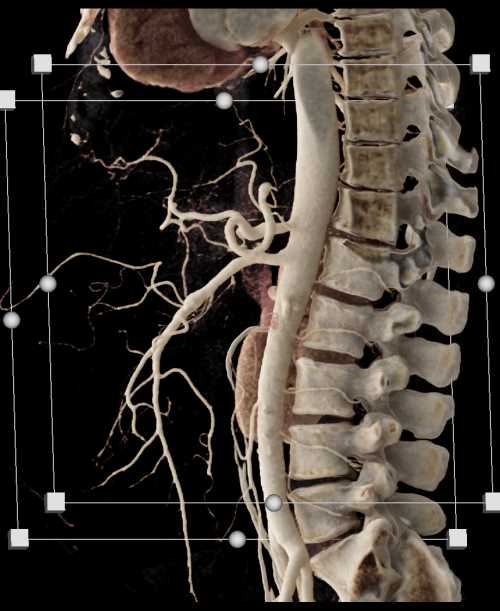

Diagnosis

SMA Stenosis